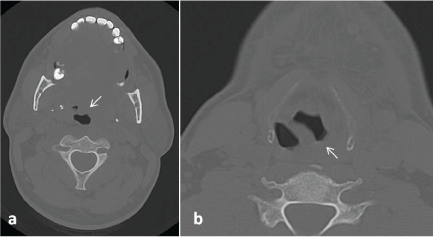

On USG; soft tissue thickening and tissue edema was seen in bilateral submandibular region, submental area and upper portion of the neck. Subsequently; CT was perfomed. CT revealed heterogeneous hypodense soft tissue thickening narrowing the air column in the left portion of the oropharynx at the level of the tongue base (Figure 1a). Left pyriform sinus is also seen as obstructed (Figure 1b). Neck MRI is performed with a clinical and radiological suspicion of LA and to be more confident about excluding a possible underlying malignancy. Neck MRI demonstrated subcutaneous soft tissue swelling and diffuse wall thickening of superior larynx, nasopharynx, oropharynx and hypopharynx (Figure 1). A cystic lesion with a 4.5 cm sized peripherally contrast enhancing was observed in the left peritonsillar area; diffusion restriction being demonstrated lesion was consistent with abcess (Figure 2 and Figure 3). In the submandibular and jugulodigastric areas, multiple LAPs were seen whose short axis was greater than 2 cm with a thickening cortex was observed. A significant clinical improvement was seen after iv amikacin and prednisolone initiation in patient who underwent surgical debridement. Cervical lymph node biopsies were reported as reactive hyperplasia on microscopic examination and surgically debrided tissue was pathologically confirmed as granulation tissue. Vancomycin and metronidazole were added to the antibiotherapy treatment and the patient was discharged with complete recovery.

Figure 1: a) At the level of the tongue base, heterogeneous hypodense soft tissue thickening narrowing the air column is seen in the left portion of the oropharynx (arrow); b) Left pyriform sinus is seen as obstructed (arrow).